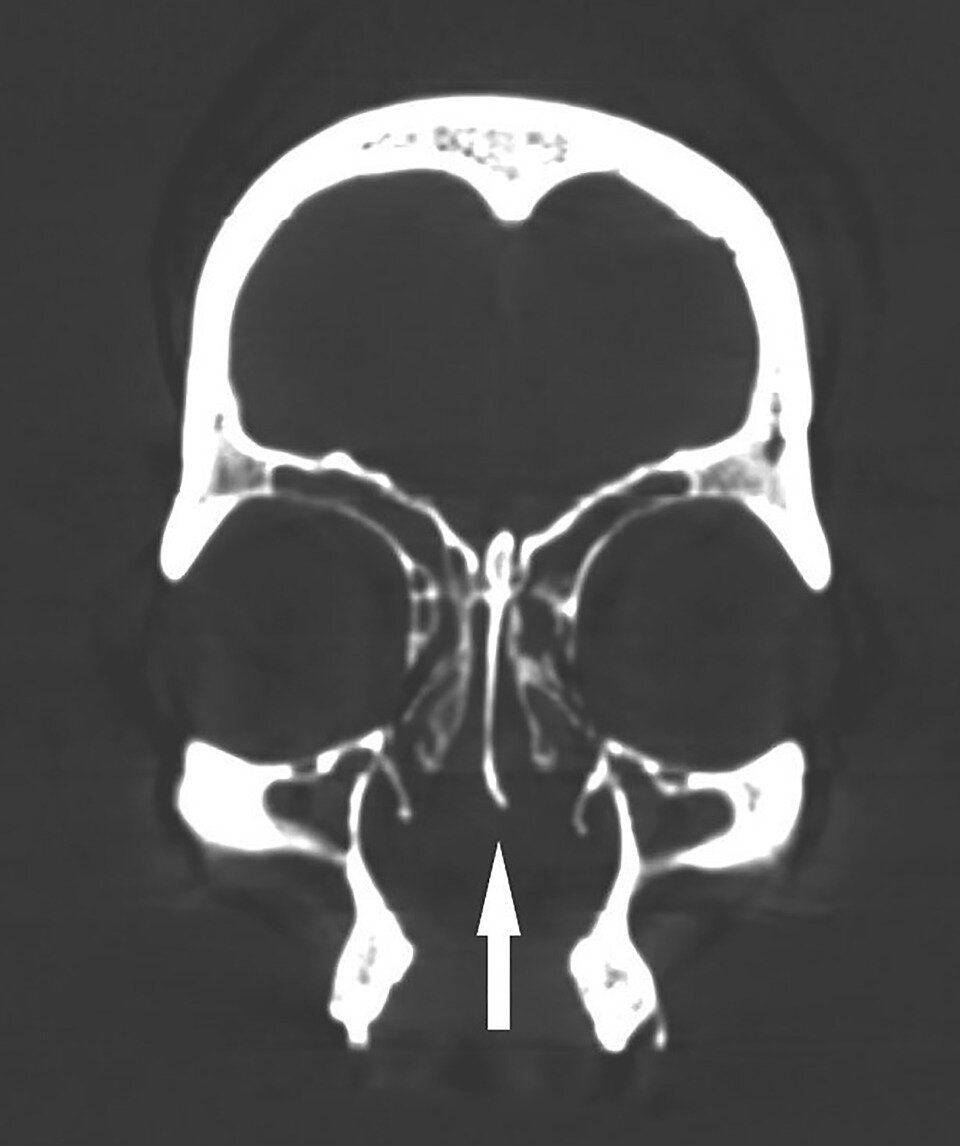

Проанализировав останки 42 человек, исследователи обратили особое внимание на скелет одного взрослого. Он принадлежал мужчине, умершему в возрасте примерно 50 лет. Ученые обнаружили у него крупную двустороннюю расщелину твердого неба, которая, по их мнению, представляет собой врожденный порок развития, а не результат полученной травмы или какого-либо приобретенного заболевания.

При этом вместе с черепом до наших дней сохранился обтуратор — приспособление, использовавшееся для закрытия дефектов твердого неба, чтобы не допустить ненормального сообщения между полостями рта и носа. Ученые отметили, что, по-видимому, он каким-то образом фиксировался в полости, но никаких приспособлений для этого не сохранилось. Возможно, он крепился к зубам. Авторы новой статьи сообщили, что этому предмету будет посвящена отдельная публикация.